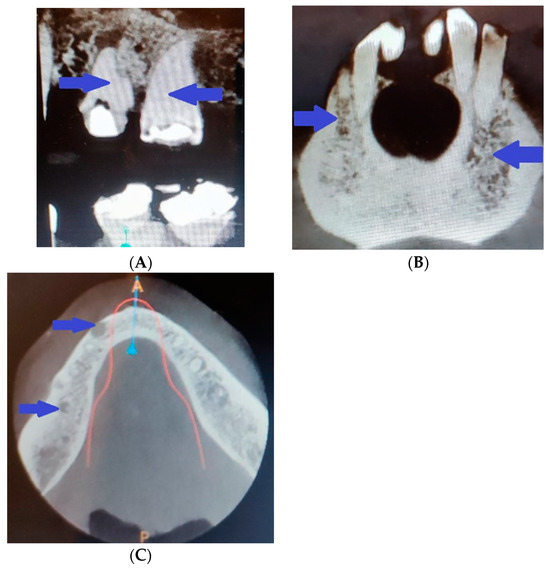

In addition, there was pathological involvement of the teeth in the patient. The pulp calcifications and obliteration of the pulp cavity revealed through radiography during an in vitro procedure (Figure 7A) made treatment of the asymptomatic granulomas impossible, and five teeth were extracted. The imaging study also revealed the spongy bone structure (Figure 7B) and some cystic masses (Figure 7C).

Figure 7.

Radiography revealing (A) pulp calcifications and obliteration of the pulp cavity; (B) spongy bone structure; (C) some cystic masses.